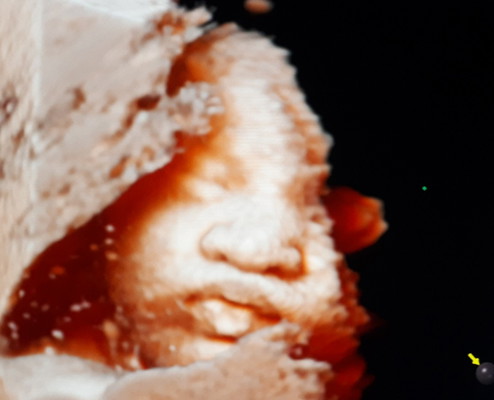

ภาวะทารกโตช้าในครรภ์

เริ่มจะน้อยใจแล้ว ปาก จมูก ไม่เหมือนแม่เลย 😅 36+1 แล้วค่ะ แม่อยากแตกแล้ว น้องมีภาวะโตช้าในครรภ์ วันนี้รอลุ้นว่าคุณหมอจะตกลงกันยังไง จะเร่งคลอดหรือยื้อให้เจ็บครรภ์คลอดเอง